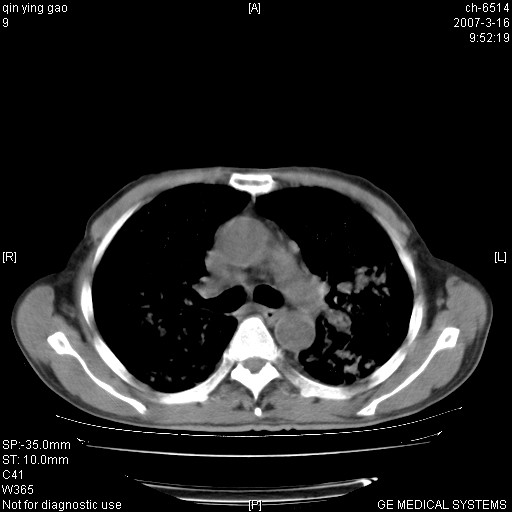

男,64岁.乏力2个月,畏寒、发热1月余。体重下降。血沉加快,白细胞不高。

双肺以中上肺野为著斑片状.结节壮密度增高影 左上肺前段可见小类圆钙化灶 纵隔淋巴结无明显肿大

双肺以中上肺野为著斑片状.结节壮密度增高影,纵隔淋巴结无明显肿大。考虑:

病变以两肺上野为著,部分病灶有钙化,纵隔窗显示病灶有新老不一,这个首先和结核脱不了干系,还有部分病灶有融洽的倾向,肿瘤也不能完全排出